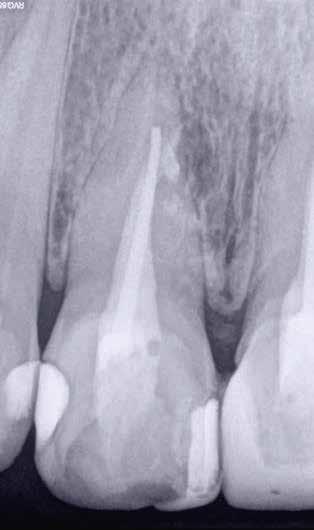

1. a–f ábrák: A cingulumon keresztül gömbfúróval kialakított hozzáférés a trepanációs kavitás labiális irányba történő túlzott mértékű kiterjesztését eredményezheti, és ez lényegesen növelheti a perforáció esélyét (a). A guttapercha átsejlik a lágyrészek alatt (b). Klinikailag igazolt perforáció (c). A preoperatív sagittális irányú CBCT-szeleten jól látható a labiális perforáció (d). Labiális irányú perforáció (fekete nyíl; e). A tényleges gyökércsatorna (piros nyíl; f).

A frontfogakban történő hozzáférési nyílás kialakítása

A frontfogakban a hozzáférési nyílás kialakítását hagyományosan a fogak linguális vagy palatinális felszínén, a cingulumon keresztül egy gömbfúró segítségével kezdjük. A linguálisan elhelyezkedő kiemelkedés teljes eltávolítása, továbbá a pulpaszarvak teljes feltárása egy háromszög alakú hozzáférési nyílást eredményez. 7 Ezt a módszert a fogak esztétikai megjelenésének megőrzése érdekében fejlesztették ki. Ez azonban időnként a saját foganyag indokolatlan eltávolításával, a trepanációs kavitás labiális irányba történő túlzott kiterjesztésével, perforációval, valamint a fog kritikus helyen, a pericervikális dentin (PCD) területén történő meggyengítésével jár (1. a–f és 2. a-b ábrák). 19 Felmerült, hogy a pericervikális dentin rendkívül fontos szerepet játszik a rágóerő gyökerek irányába történő továbbításában, és elképzelhető, hogy a gyökérkezelt fogak hosszú távú megtartása szempontjából a legfontosabb tényező az ép pericervikális dentin megőrzése lehet. 20 A cingulumon keresztül történő hozzáférési nyílás

kialakítása során fennáll a fog labiális irányú perforációjának veszélye, mivel ilyenkor a foganyag elvételét labiális irányú fúrótartással kezdjük. Nemrégiben újragondolták a